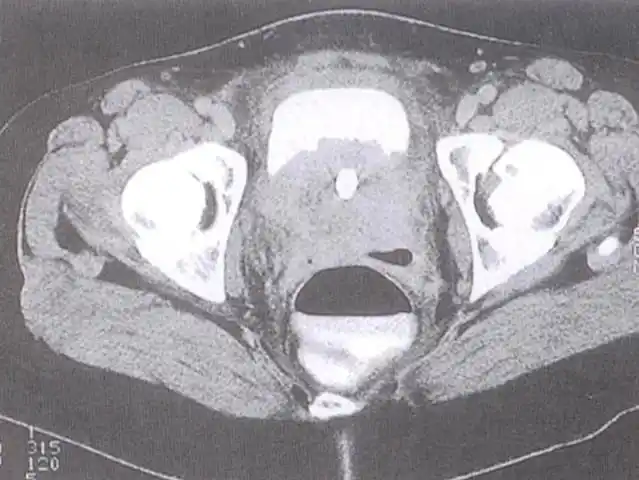

盆腔囊性病变,部位很重要|前庭大腺囊肿|尿道旁腺囊肿|盆腔囊性|-健康